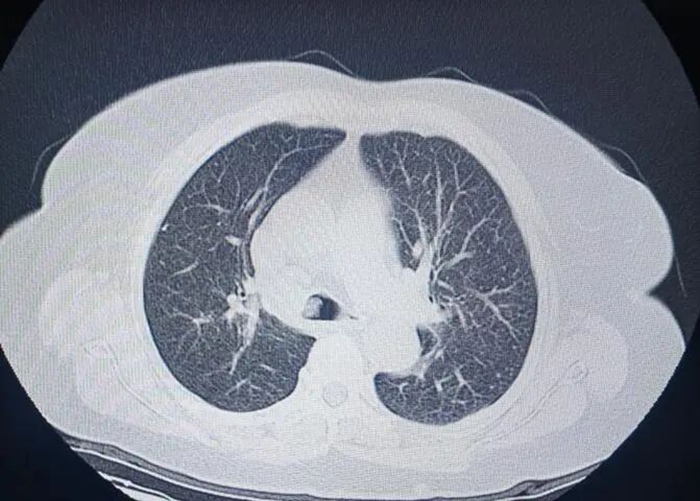

呼吸科王娟医生随即使用支气管镜探查,发现患者气管内积血,隆突上肿瘤阻塞大部分气管下段并完全阻塞右主支气管,左主支气管开口被肿瘤遮挡1/2,左下叶支气管内大量积血,医护团队立即快速吸引清理气道积血,保障左肺有效通气、防止窒息,同时紧急联系心内科会诊,刘燕医生同步完善心电图及血气分析,二线黄倩医生及RICU胡嘉艺医生也闻讯赶来支援。内镜中心护理团队张晨阳、石雅欣等在隗海朦护士长指挥下,克服患者躁动、血管条件极差的困难,迅速配合完成抽血送检心肌酶等检查。心内科马岩医生接到电话后跑步赶到,结合心电图及监护表现,排除急性心肌梗死,判断为缺氧诱发的心肌缺血及心律失常。